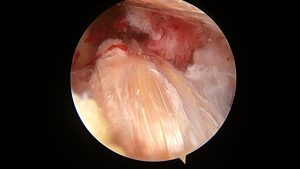

後十字靭帯再建術

先日、東京女子医科大学整形外科教授の岡崎賢先生を招いて

後十字靭帯(PCL)再建手術を行いました。

私は、ほとんどの膝の手術を一人で行っていますが、

この手術だけは、一人で行うことは難しいと考えています。

できなくはなくても、手術時間が長くなりすぎると術後の腫れや痛みが強くなり、

患者さんに負担をかけてしまいます。

関節鏡手術を完全にこなせる医師二人がかりで行うことで、安全確実に、短時間で

手術を終えることができます。

岡崎先生は膝関節手術のスペシャリストであり、

学会や勉強会の演者として引っ張りだこです。

手術の前後や合間に、膝関節節手術の最近のトレンドを聞けたり、

ディスカッションすることができ、良い刺激をいただけます。